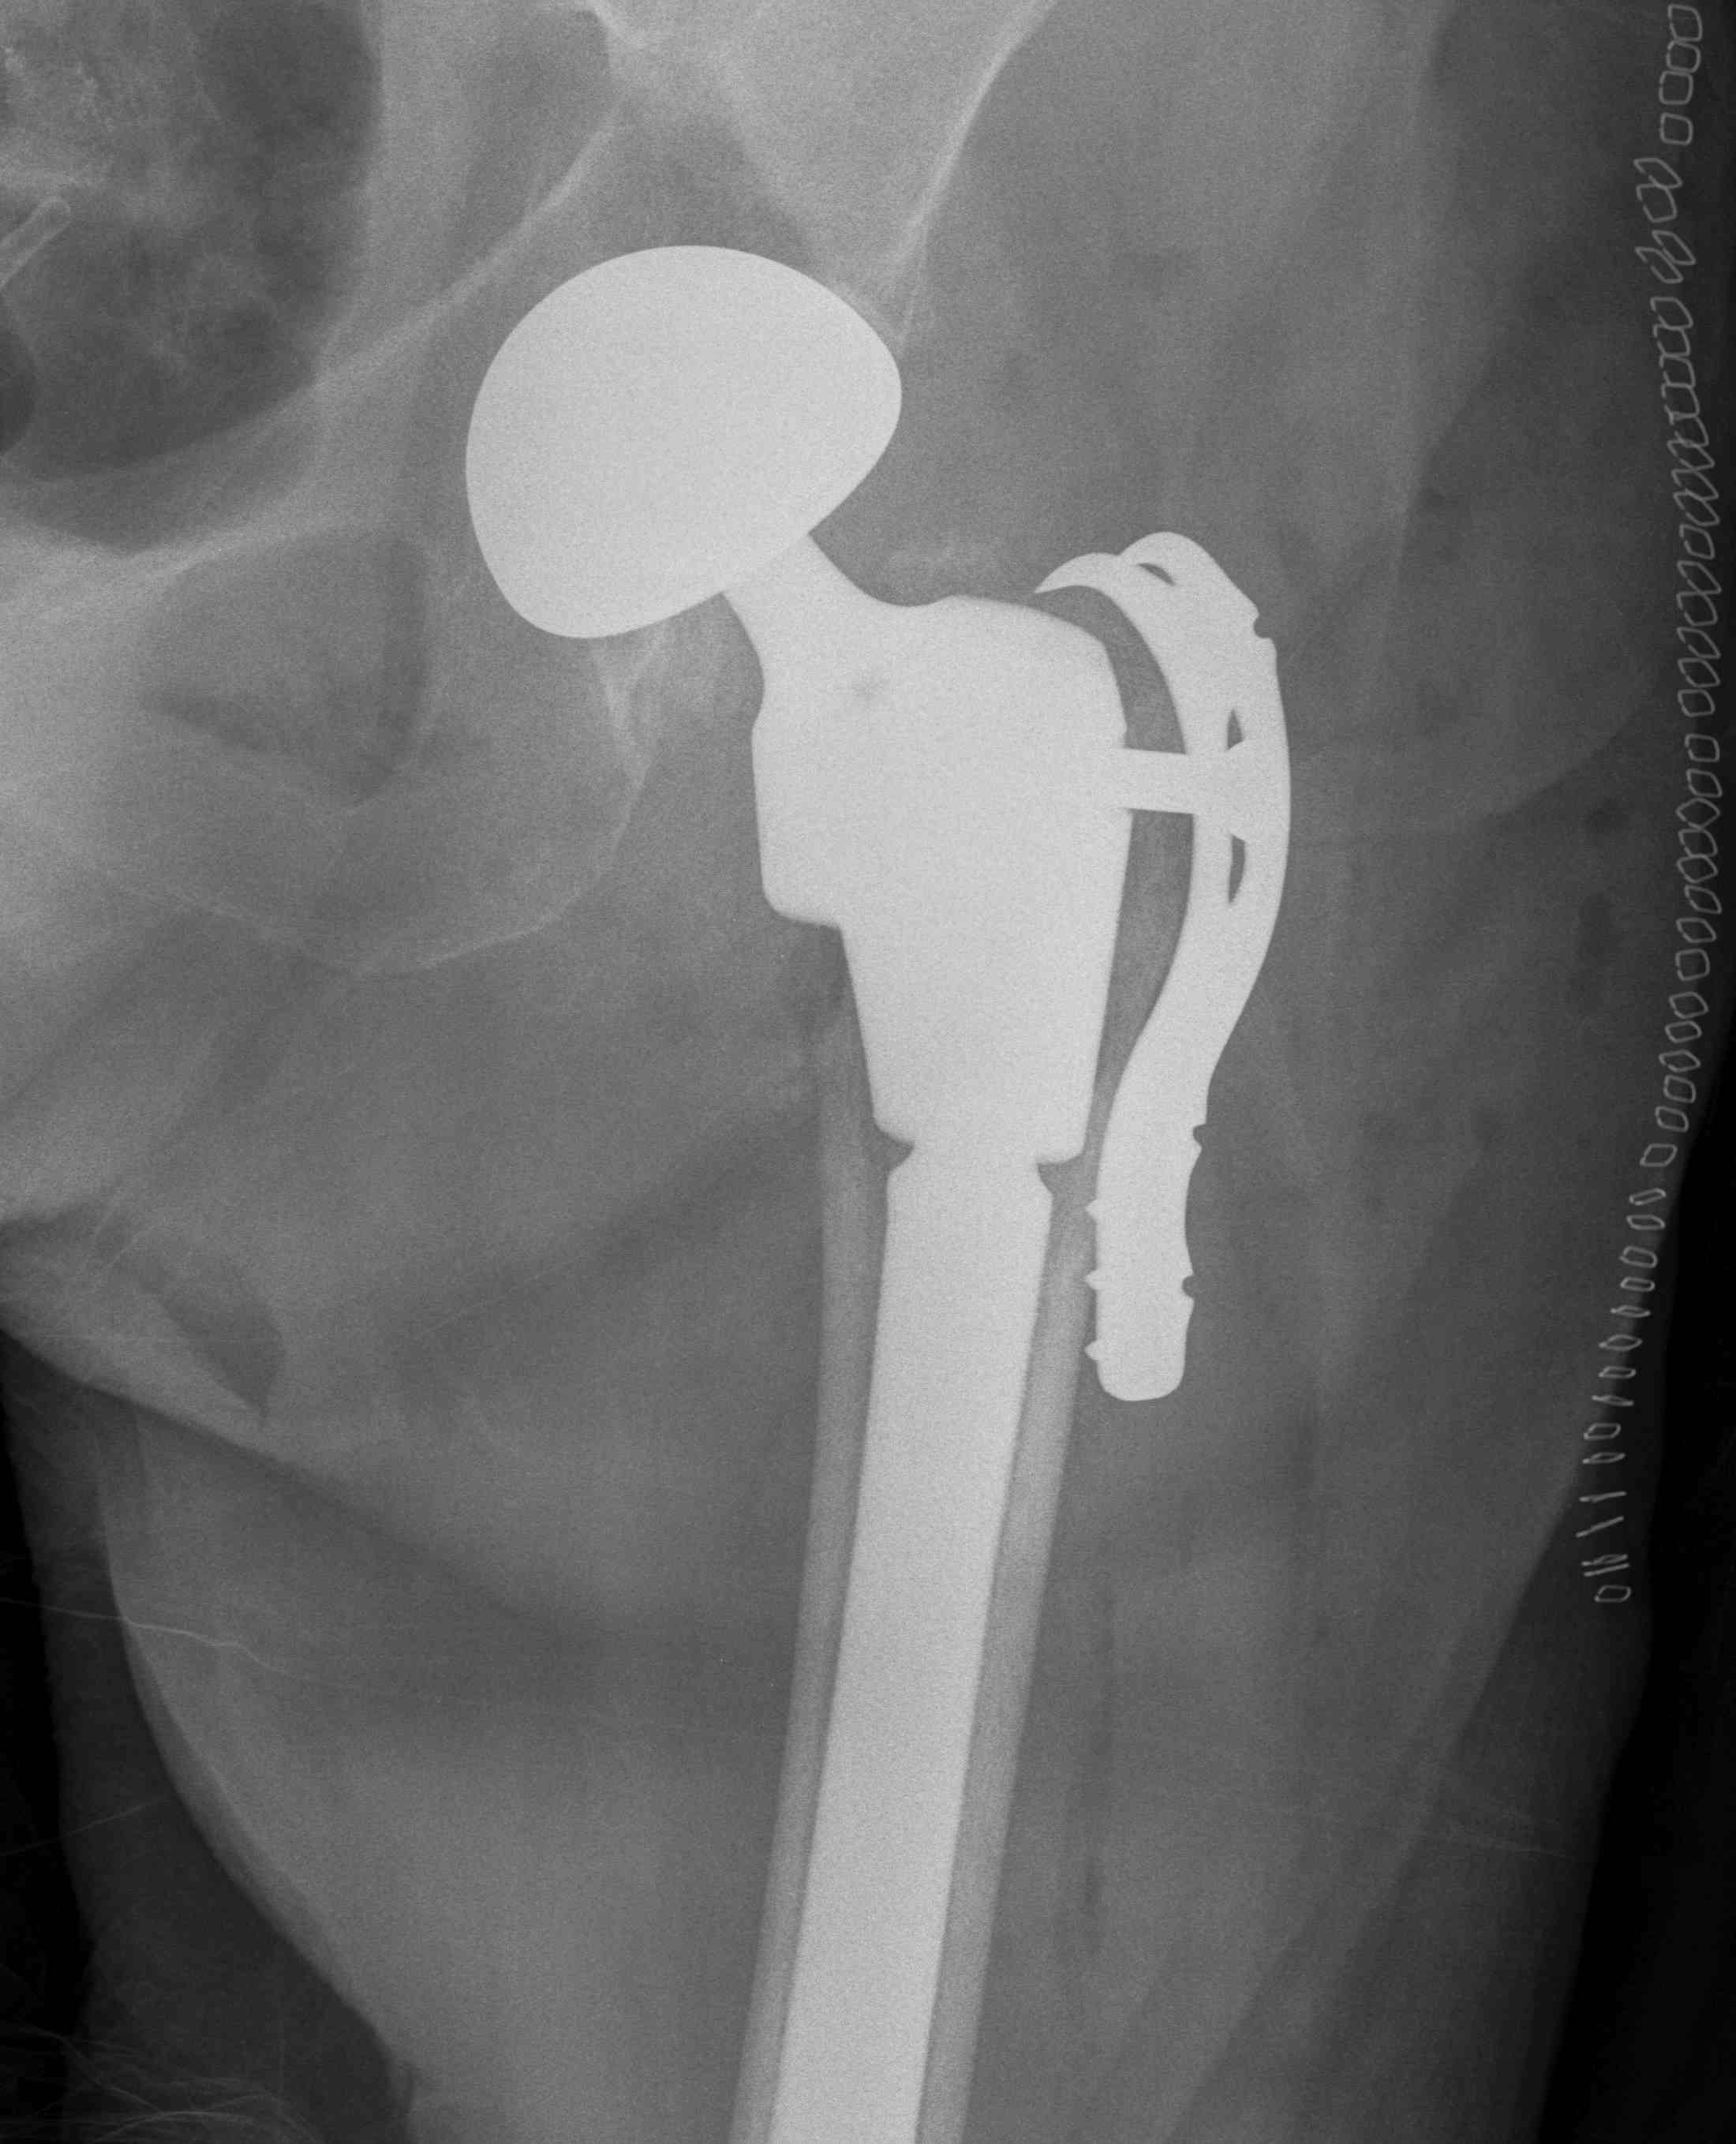

Hemiarthroplasty / Total hip replacement

Indications

- severe comminution

- salvage of failure of previous fixation

Technical

- may need calcar replacement

- may need greater trochanter fixation

THA Issues

A. Femoral component

- cement will come out screw holes

- Option 1: leave screws in laterally, and strip medially to insert small screws

- Option 2: use uncemented stem

B. Length of femoral stem

- should bypass distal screw hole by 2 cortical diameters

C. Calcar

- normal stem usually sufficient if LT healed back on

- otherwise may calcar replacing

D. Greater trochanter

- may need plate / cables to reduce